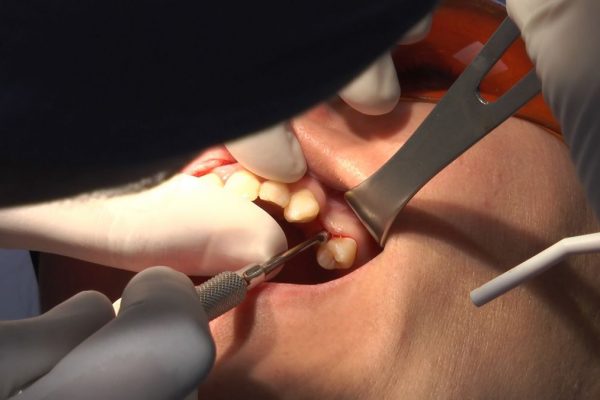

W ostatni weekend czerwca 2018 roku kursanci II Sezonu Preludium Implantologii odbyli piątą, finałową sesję, która w całości podporządkowana była praktyce. W ciągu dwóch dni zabiegowych Lekarze uczestniczący w szkoleniu przeprowadzili szereg zabiegów pod kierunkiem dr n.med. Violetty Szycik. Wszczepili 17 implantów oraz przeprowadzili ekstrakcje i zabiegi regeneracyjne kości. Zabiegi były wykonywane także w sedacji dożylnej z udziałem specjalisty anestezjologii i intensywnej terapii dr Jolanty Grzybowskiej. Preludium implantologii to nowy program edukacyjny dla adeptów implantologii stomatologicznej, którego celem jest wprowadzenie do implantologii poprzez pozyskanie wiedzy w szerokim zakresie i uwzględnieniem szczegółów mających decydujące znaczenie dla powodzenia leczenia implantologicznego. Ale tak jak wszystkie szkolenia w Instytucie Vivadental, w tym wiodące Practiculum Implantologii, zorientowane jest na praktyce i samodzielnym wykonywaniu zabiegów pod kierunkiem Mentora. To najlepsza edukacja w medycynie zabiegowej, a zarazem najlepszy start do implantologii.